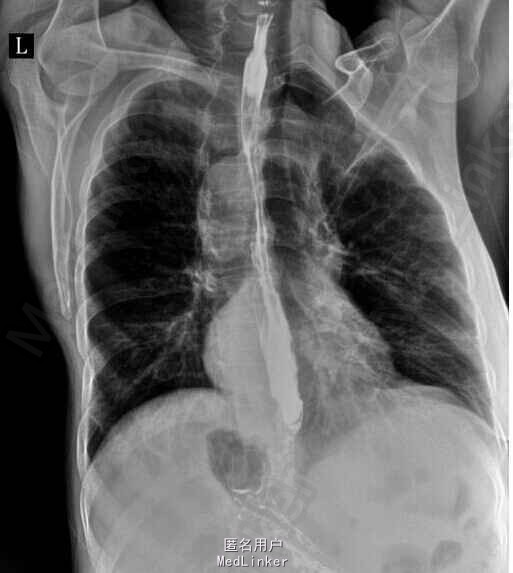

查体:慢性肝病体征,肝掌,蜘蛛痣阳性,腹水征阳性,压痛,反跳痛阴性。 辅查:肝功能示:谷丙260,谷草111.9,白蛋白34,总胆121,直胆80,ALP179,GGT200,凝血四项PT19,PTA41,甲胎蛋白86,HBV DNA7.9x10E4,肝炎系列未见异常,肝彩示肝硬化,食管钡餐示串珠样改变

诊断:乙肝肝硬化失代偿期、食管胃底静脉曲张 治疗:常规护肝退黄降酶治疗,制酸护胃,输血浆,白蛋白,利尿等对症支持治疗,予博路定抗病毒治疗。